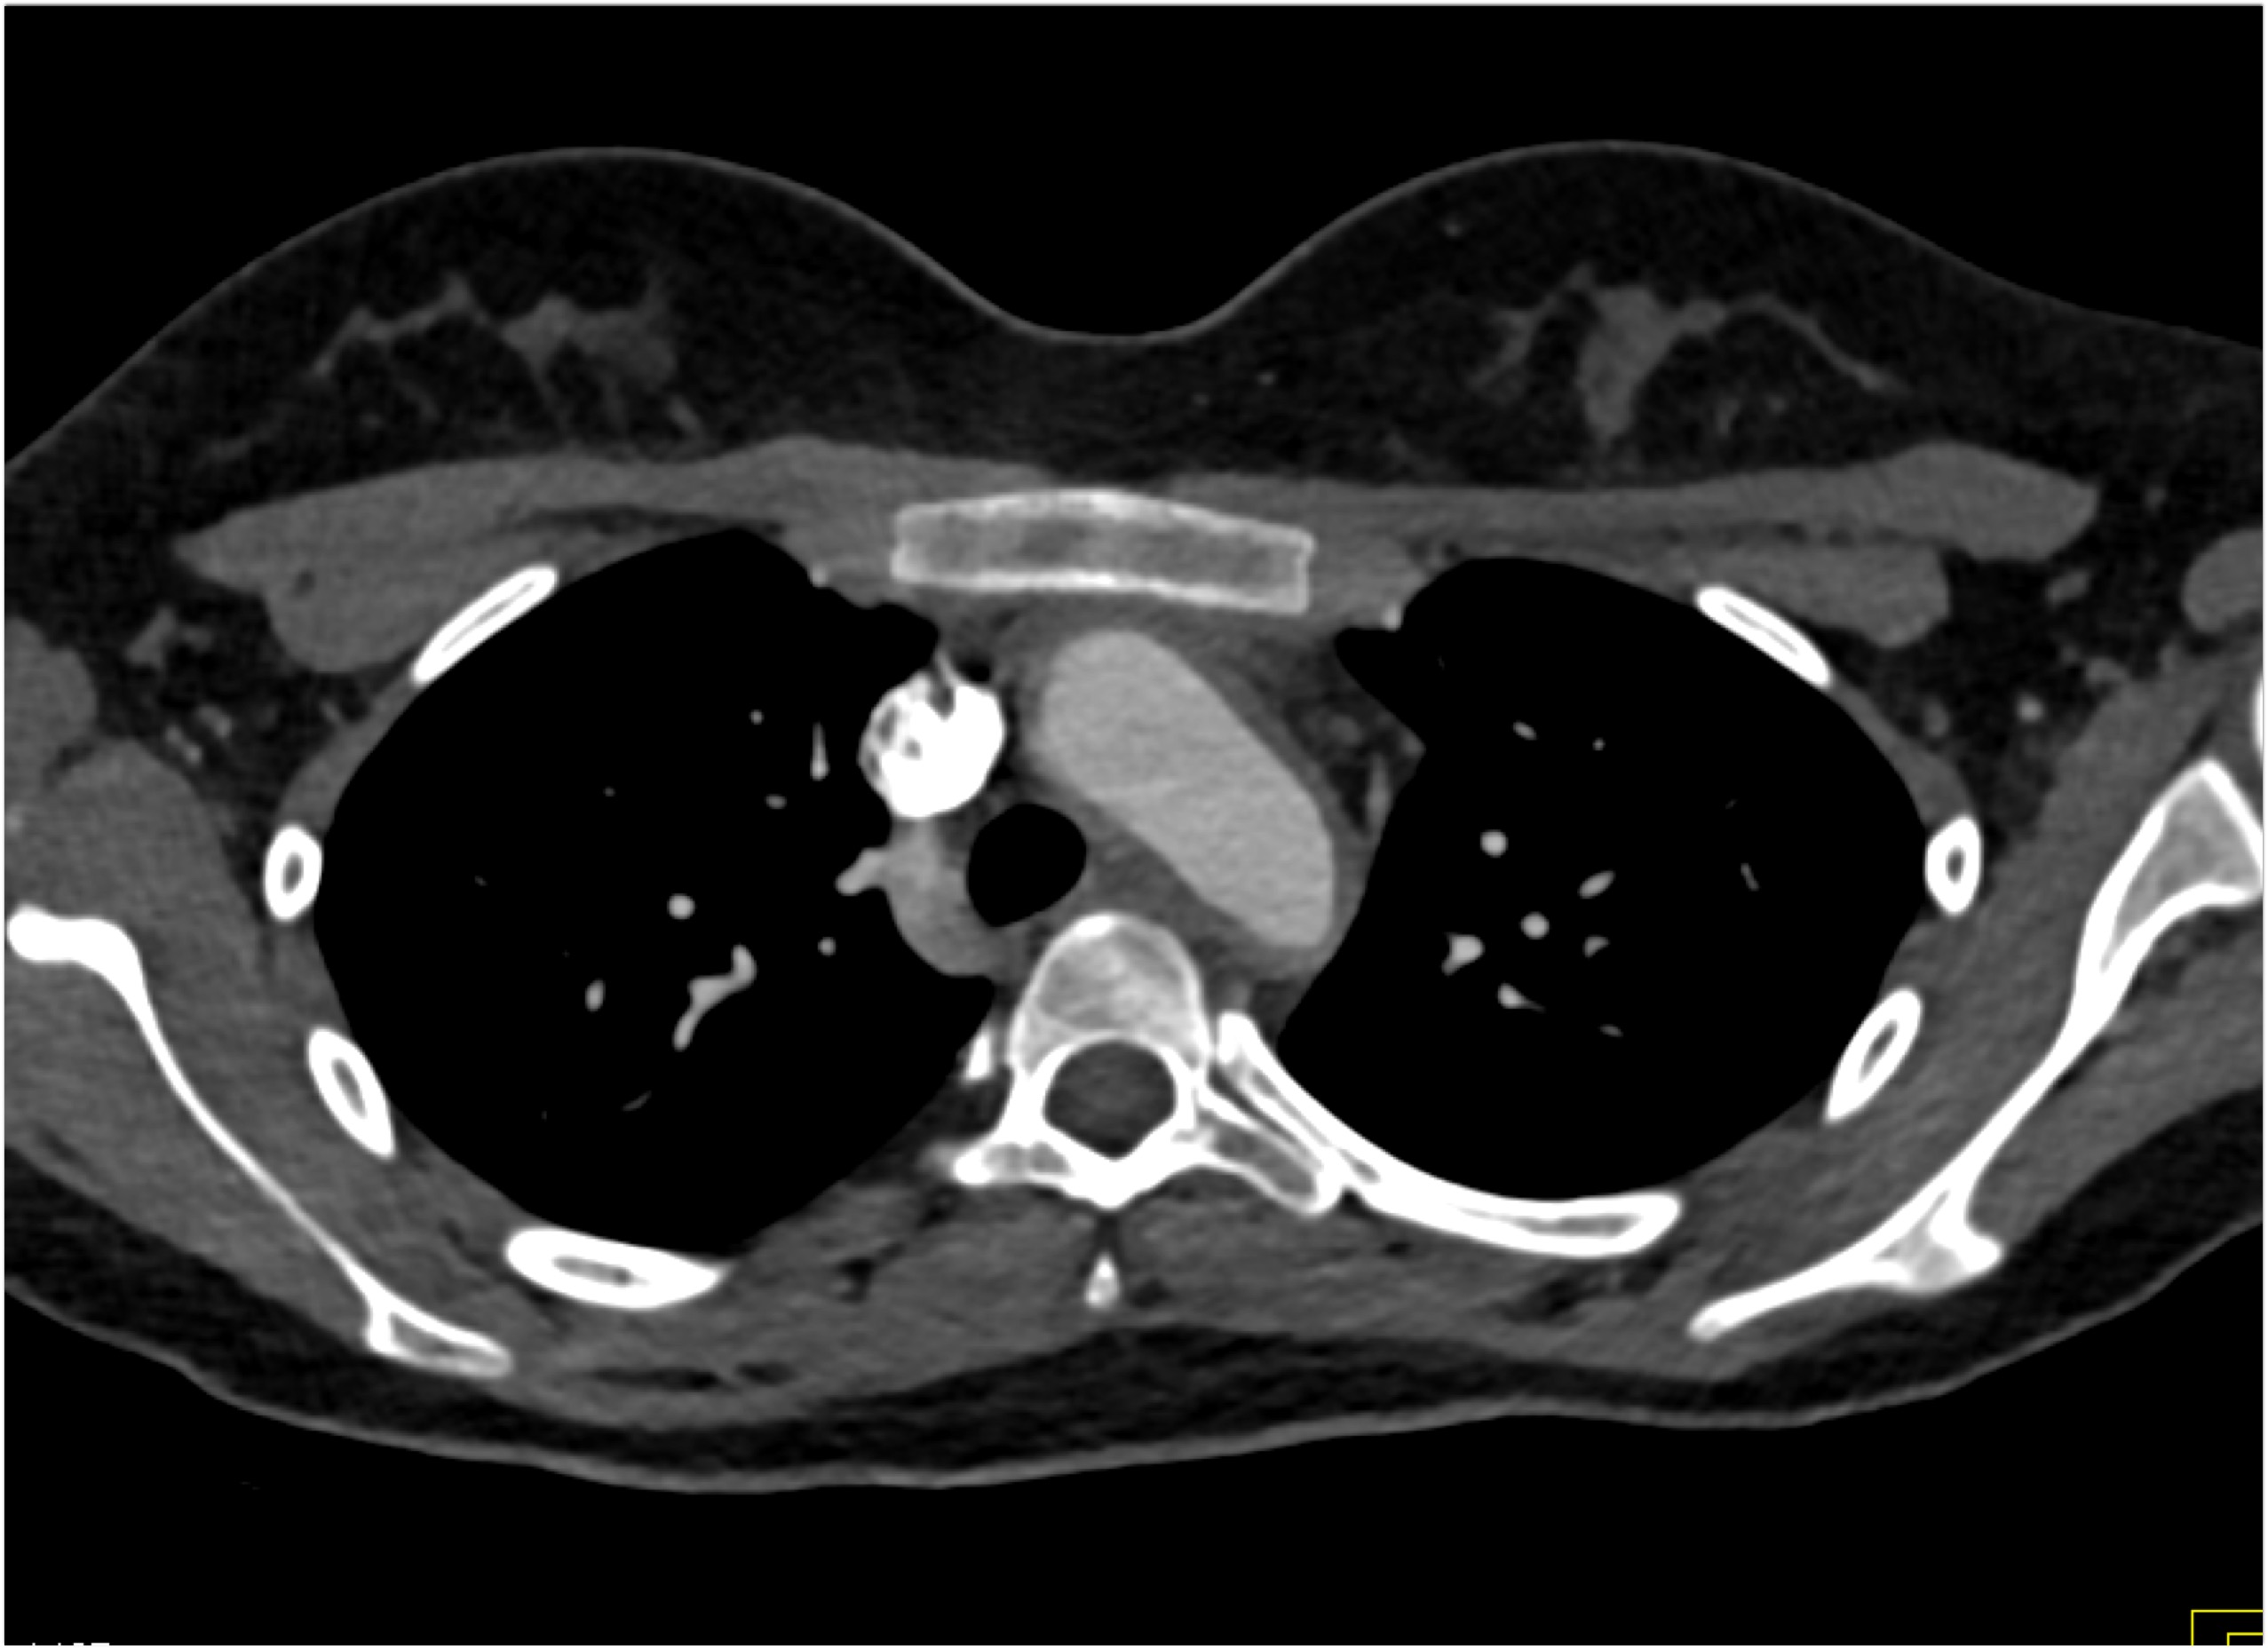

7) The most likely diagnosis in this case is?

Ehlers Danlos disease

Kawasaki disease

Takayasu’s aortitis

Ig4 vasculitis